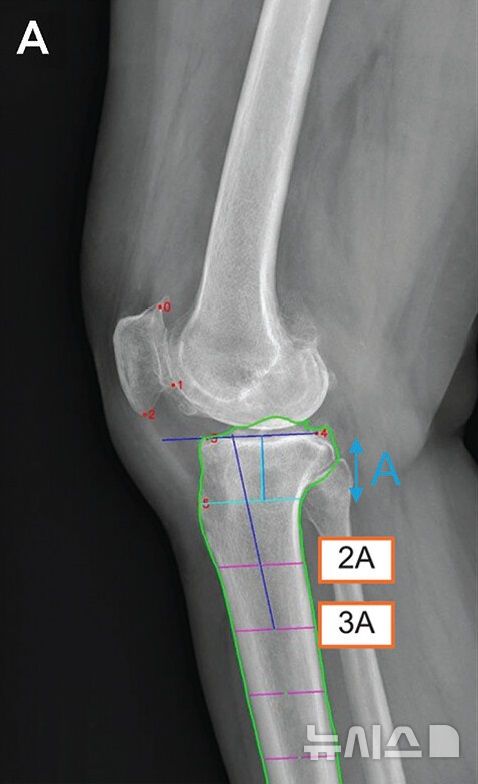

[서울=뉴시스] 딥러닝 모델의 측정 매커니즘. 6개의 해부학적 기준점(빨간 점)을 자동 인식한 후, 경골의 관절선과 중심축(파란 선)을 결정해 경골 후방 기울기를 계산한다. (사진= 서울대병원 제공)

이 모델은 먼저 엑스레이상 무릎뼈의 6개의 해부학적 기준점(랜드마크)을 자동으로 인식하고, 이후 각 기준점을 이용해 경골의 관절선과 중심축을 결정한 다음, 이를 바탕으로 경골 후방 경사각을 자동 계산한다.